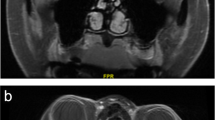

OCT plays a similar role in the assessment of ischaemic optic neuropathies as it does in assessment of optic neuritis. Acutely, optic disc swelling can be diagnosed and quantified using pRNFL thickness measurements. Within 2 months, 80% of patients subsequently show pRNFL thinning, with progressive thinning and thus optic disc atrophy occurring between months 2 and 4, with stability typically reached at month 6 [65,66,67]. As with optic neuritis, thinning of the mGCIPL has been shown to occur much earlier than pRNFL thinning. It can occur as early as 2.2 days after onset of symptoms, and thinning of the mGCIPL density has been shown to be present in 62.5% of eyes at presentation [68]. Longitudinal assessment of the mGCIPL layer offers a reliable and objective tool in monitoring of these patients (Fig. 10). Furthermore, the pattern of mGCIPL loss often indicates the degree and pattern of visual field loss [69,70,71], which in non-arteritic ischaemic optic neuropathy (NA-AION) is often altitudinal.

She was diagnosed with right arteritic anterior ischaemic optic neuropathy (A-AION) due to giant cell arteritis (GCA). Spectral domain optical coherence tomography (SD-OCT) imaging demonstrates progressive thinning of the macular ganglion cell layer (mGCL) from onset, shown here at 3 weeks and 8 weeks post presentation.